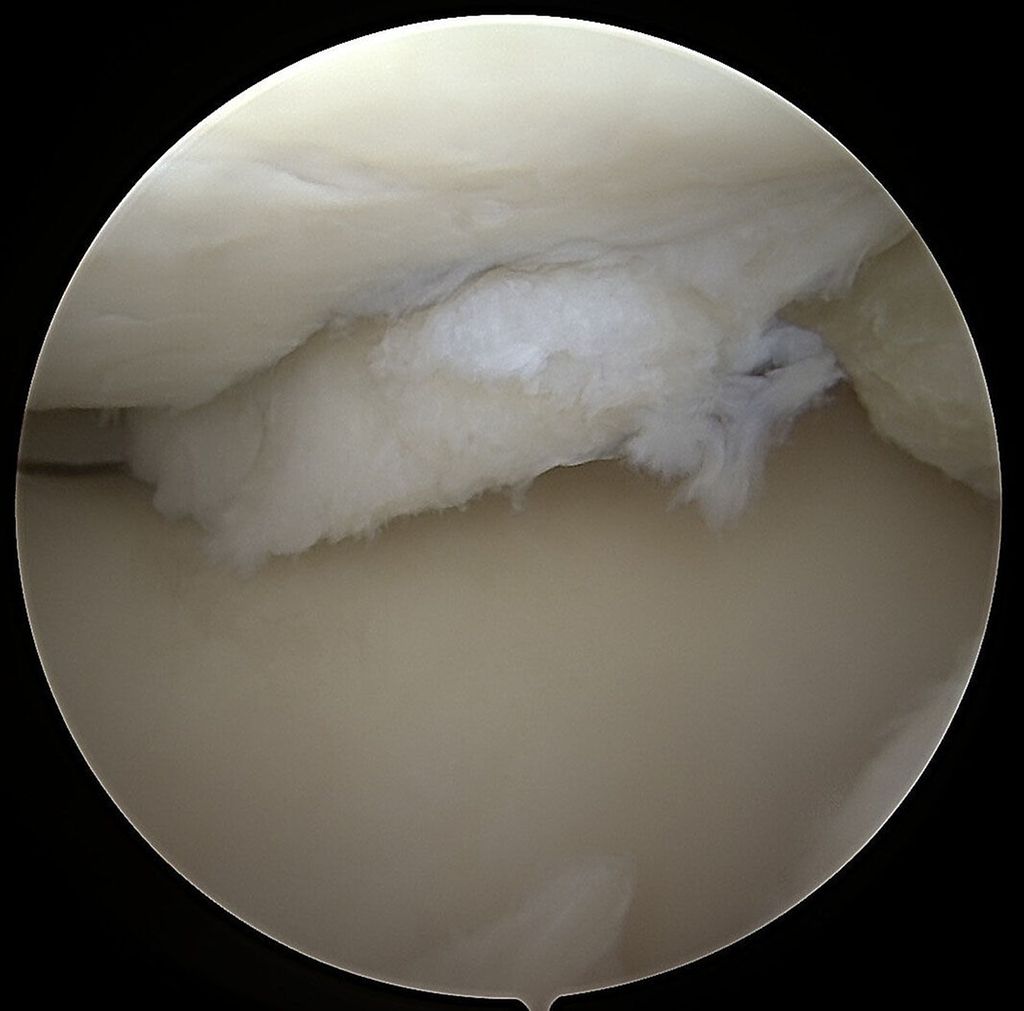

Abb. 2: Das arthroskopische Korrelat des MRT-Bildes zeigt ein instabiles Knorpelregenerat mit fehlender Integration und beginnender Delamination